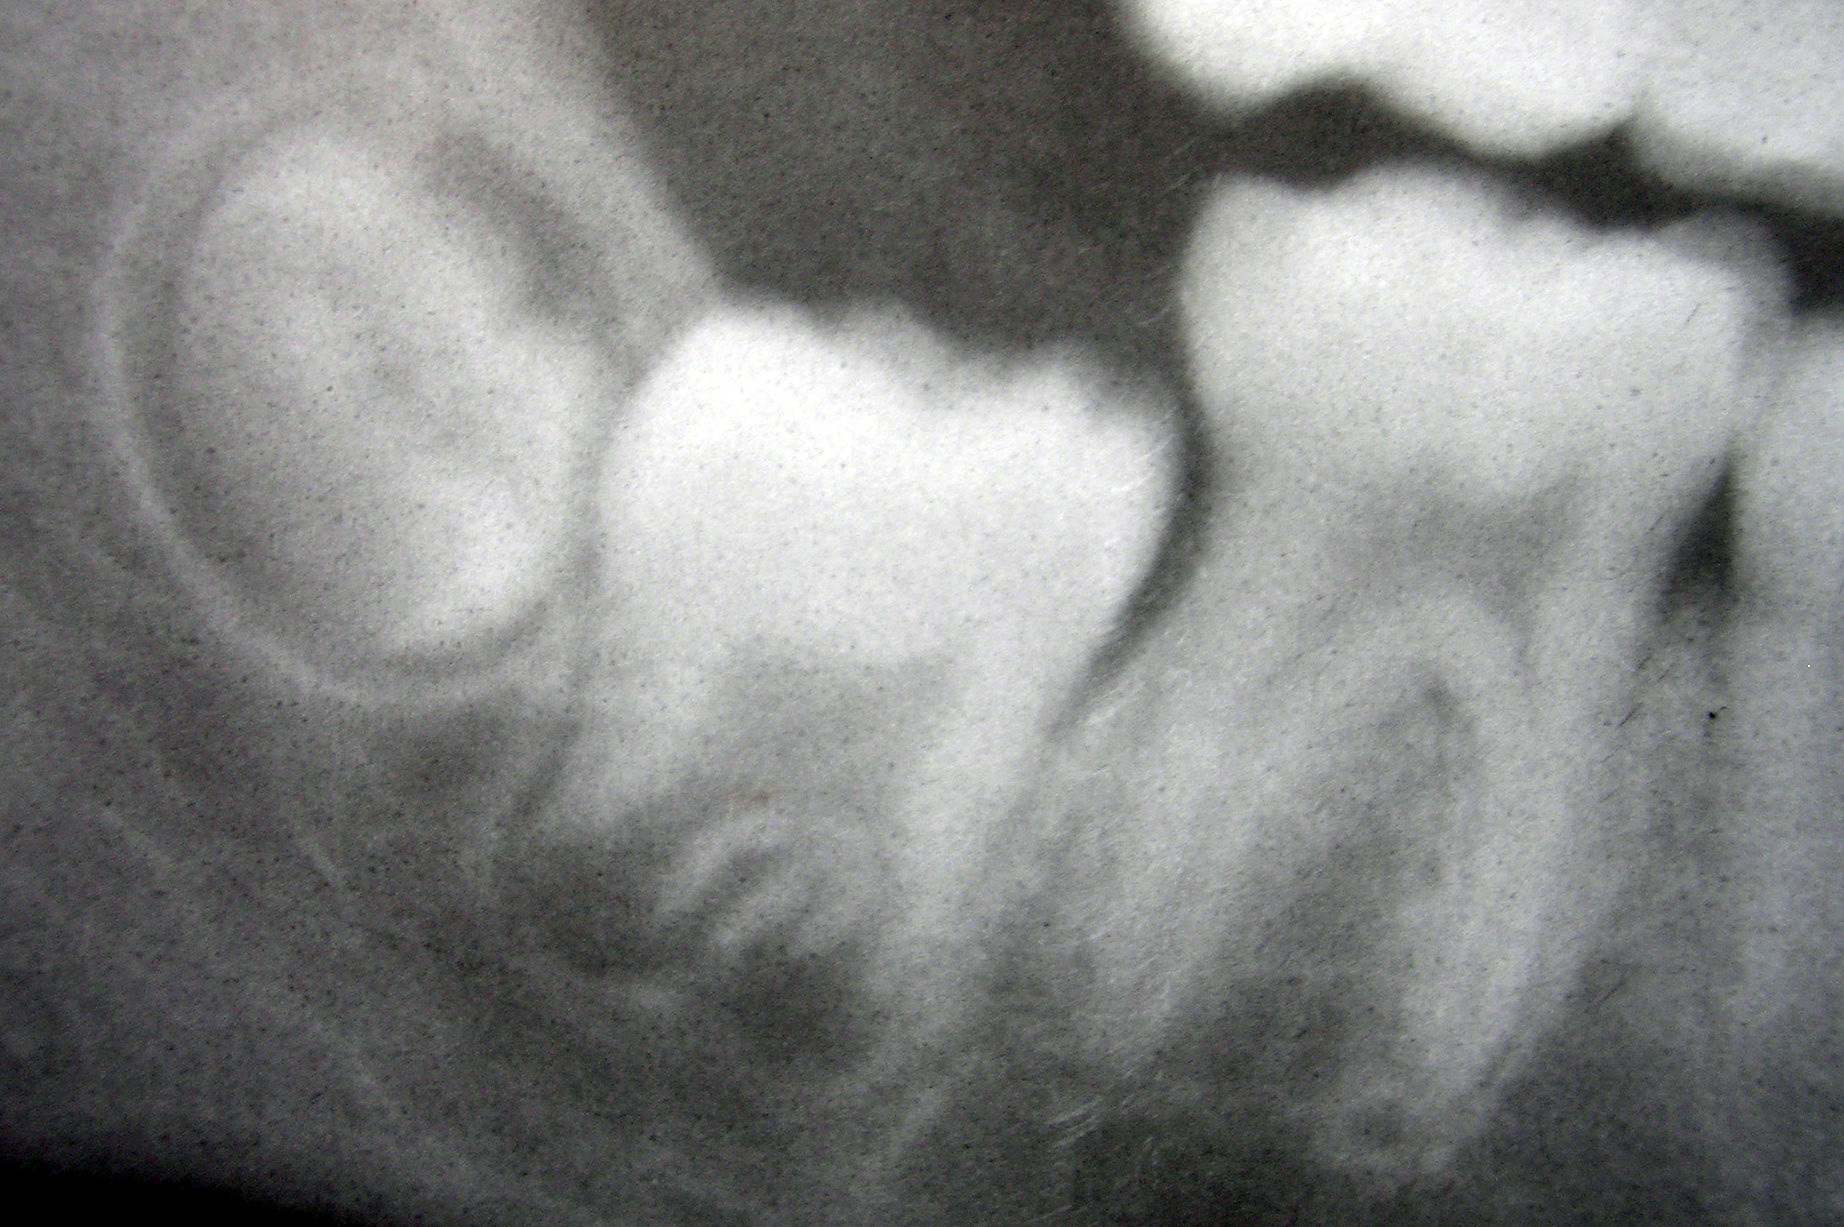

Врач Патлатая: хлоргексидин снимет боль при прорезывании «восьмерок»

Доктор Надежда Патлатая проинформировала, как правильно ухаживать за полостью рта при прорезывании зубов мудрости, пишет

Эксперт Государственного университета просвещения заявила, что снять боль можно за счет полоскания рта антисептиками. Сильную боль можно снять при помощи противовоспалительных и обезболивающих препаратов.

Для полоскания подойдут хлоргексидин или мирамистин. По утверждению хирурга, рост «восьмерок» может сопровождаться повышением температуры и отеком. При таких симптомах нужно обратиться к стоматологу.

Фото: No machine-readable source provided. Own work assumed (based on copyright claims)., No machine-readable author provided. Dozenist assumed (based on copyright claims).reative Commons Attribution-Share Alike 3.0 Unported license.,